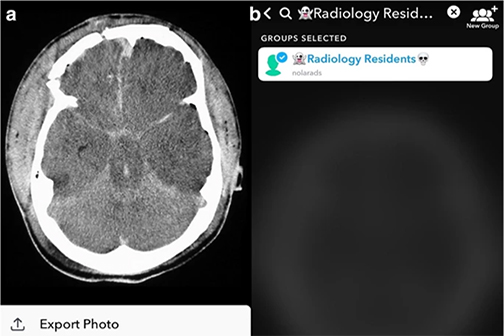

LSU Health New Orleans Discovery May Complement Recovery from Ischemic Stroke

A study led by Nicolas Bazan, MD, PhD, Director of the LSU Health New Orleans Neuroscience Center, pinpointed which cells within specific areas of the brain are involved in post-stroke response and found that the delivery of precursors of Elovanoids, a class of molecules that synchronize cell-to-cell communication and neuroinflammation/immune activity in response to injury, improved neurological deficit in an experimental model of ischemic stroke. More

LSU Health New Orleans Researchers Discover Potential New Rx Strategy for Ischemic Stroke

A study conducted by scientists at LSU Health New Orleans’ Neuroscience Center of Excellence reports that the additive neuroprotection of a combination of two omega-3 fatty acid-derived signaling molecules is more effective in protecting brain cells and increasing recovery from stroke in an experimental model than a single drug. More